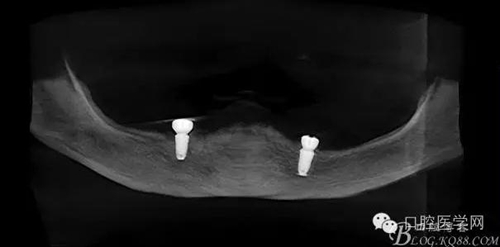

種植體植入后

種植覆蓋全口義齒3個月后上球型基臺

種植覆蓋全口義齒下頜牙槽嵴吸收嚴重,若沒有種植體無法固位。